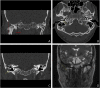

Case presentation: This case report describes a large chondroblastoma (diameter, approximately 37 mm) that occurred in the TMJ. The tumor was sufficiently aggressive to destroy the TMJ, mandibular condyle neck, external auditory canal (EAC), mandibular fossa of the temporal bone, and facial nerve. The tumor was completely excised using a pre-auricular approach. The EAC and surgical defect were successfully reconstructed using a temporoparietal fascia flap (TPFF) and an inguinal free fat graft. There was no local tumor recurrence at the 18-month follow-up visits. However, the patient developed sensory neural hearing loss, and his eyebrow paralysis worsened, eventually requiring plastic surgery.